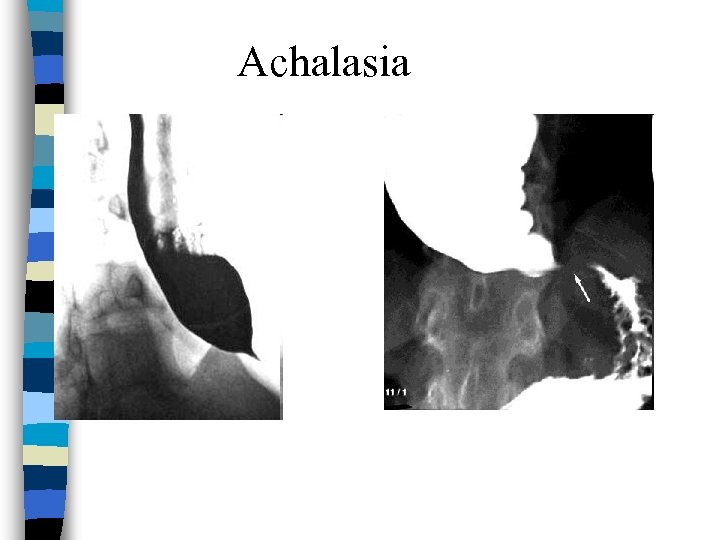

Achalasia Dx n Barium studies: – Absence of progressive peristaltic contractions during swallowing – Significant esoph dilation – Narrowed “birds beak” distal esoph (at LES) n Manometry: – Lack of peristalsis, lack of relaxation of LES

Achalasia